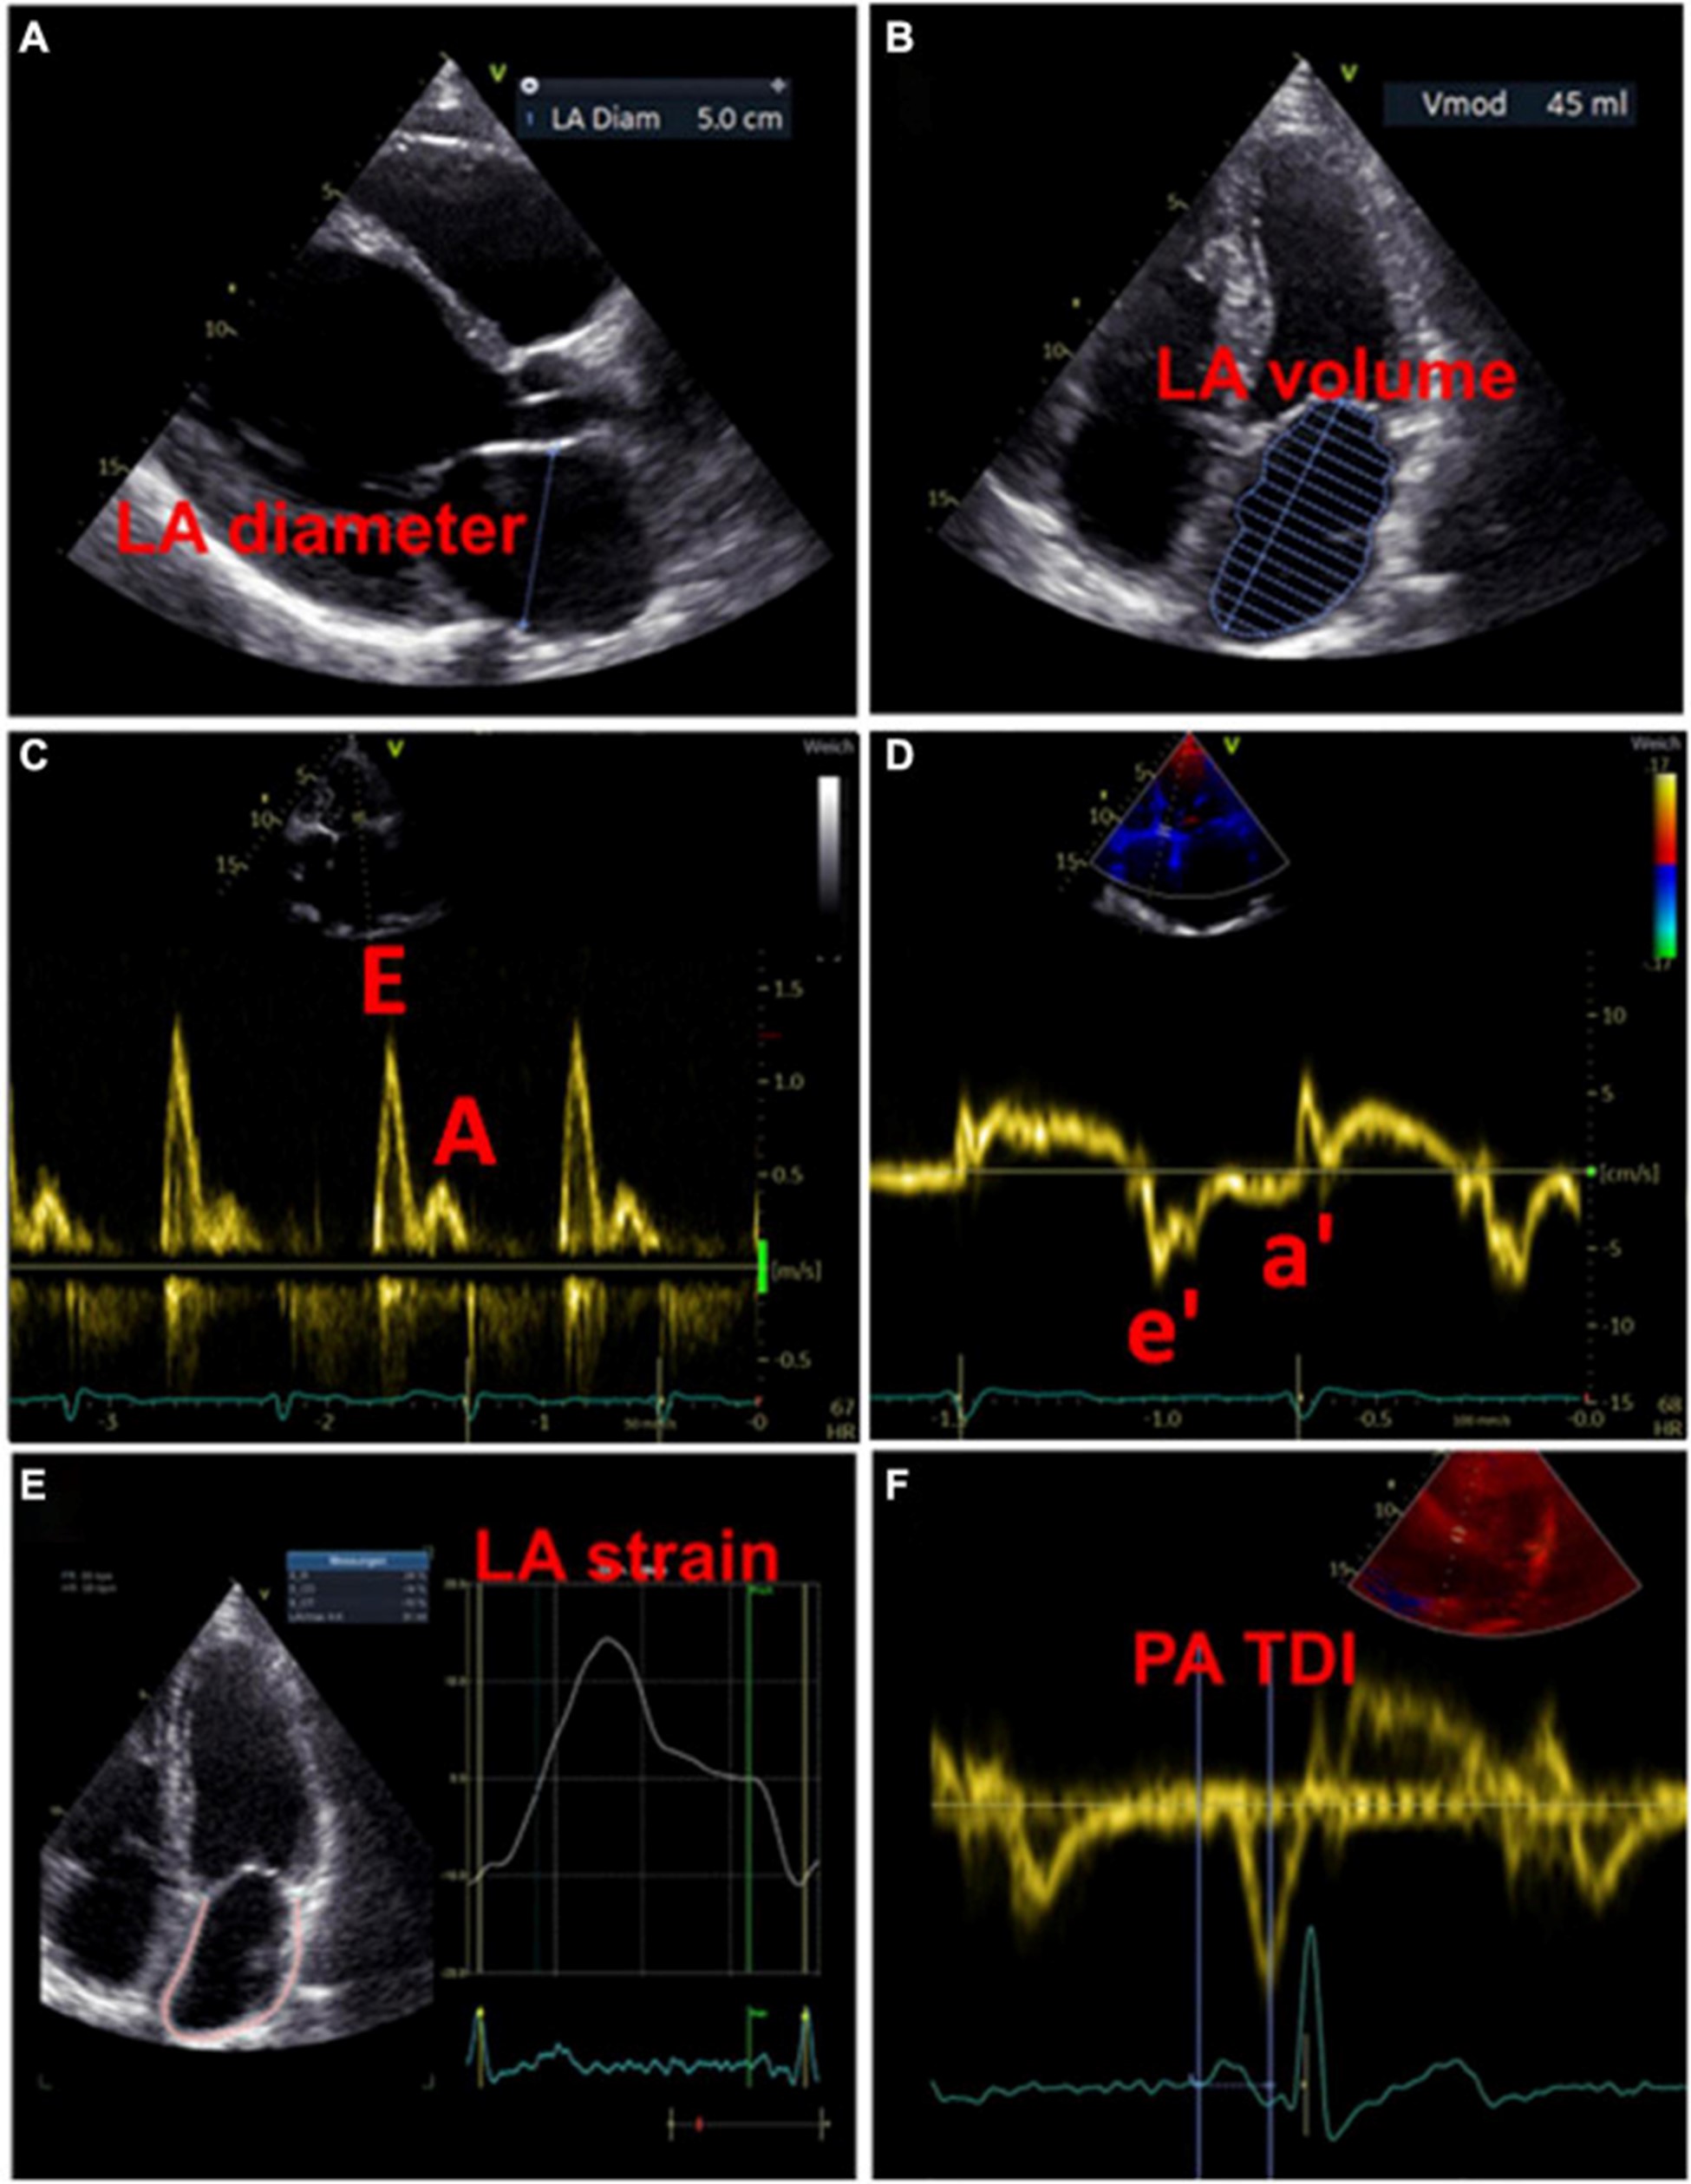

一方面,LA 扩大与心血管不良后果的发生呈正相关是众所周知的 。另一方面,扩大的 LA 也与 AF 的发生有关 。超声心动图是筛查和随访 LA 形态和功能异常患者的首选成像技术,因为它使用广泛、无创且成本效益高 。因此,超声心动图可能有助于检测 LACM。在调查超声心动图效用的研究中,LACM 的定义是证明 LA 大小异常与主要临床结果(如 AF、AF 负担、消融后 AF 复发和缺血性卒中)之间存在关联。表格1)。

左心房大小

用于估计 LA 大小的一个广泛使用的参数是 LA 直径 (图 3A)。在 AFFIRM 研究中,增加的 LA 直径与复发性 AF 相关,但与卒中风险无关 。然而,一项荟萃分析揭示了较大的 LA 直径与中风和血栓栓塞事件的发生率之间存在关联 。此外,大 LA 直径和 LA 体积指数都被证明是主要不良心血管和血栓栓塞事件的预测参数,特别是在没有 AF 的年轻患者中 。LA 容积指数更精确,因此更适合估计心房大小(图 3B)。增加的 LA 体积指数已被描述为心肌功能障碍的潜在早期标志物,并且经常出现在 AF 患者中,在更高的 AF 负担中频率增加 。此外,与似乎没有预测作用的最大 LA 体积相比,最小 LA 体积与新发 AF 和主要不良心血管事件的发生率密切相关 ( 53 – 56 )。

图 3:用于检测左心房心肌病的超声心动图测量示例。(A)测量左心房舒张期的直径。(B)左心房舒张期左心房容积的测量。(C)左心室舒张期的经口流入曲线:第一波代表 E 波(血液被动流入左心室),第二波代表 A 波(左心房主动收缩)。(D)左心室心肌运动的组织多普勒成像,结合(C)心房功能和左心室舒张末期压力的测量结果。(五)左心房的应变分析。(F)测量从 P 波开始(作为心房电活动开始)到 a' 波峰值(心房收缩的机械反应)的 PA-TDI 间隔。

除了代表结构重构的 LA 大小异常外,心房功能评估可能为左心房心肌病的存在提供进一步的重要指标。LA 扩大和 LA 排空分数降低都是 AF 患者的常见现象,LA 大小与排空分数呈负相关 。最近,Eichenlaub 等人。评估了 AF 患者的 LA 排空分数,用于诊断左心房心肌病和预测 PVI 后心律失常复发 。LACM 定义为心内膜接触标测在 0.5 mV 阈值时LA 低电压区域 ≥ 2 cm 2 。LACM 患者的 LA 排空分数低于没有左心房心肌病的患者(27 对 41%,p < 0.0001)(43)。此外,LA 排空分数 < 34% 是 LACM(曲线下面积为 0.846)和 PVI 后心律失常复发的重要预测因素(57)。

多普勒超声心动图

此外,可以通过脉冲波多普勒测量和组织多普勒成像来评估 LA 功能。LA 功能受损可能提示 LACM,在使用多普勒超声心动图的研究中,这与 AF 和 AF 负担等临床结果等同。表格1)。

过去,已经研究了许多与二尖瓣血流和舒张期心肌运动相关的超声心动图参数与 LA 功能和临床事件的关联 。然而,尚未确定适合诊断左心房心肌病的参数和相应的临界值。

虽然 LA 传导功能(以二尖瓣 E 波速度为代表)随着 AF 负荷的增加而增加,但 LA 收缩功能(以二尖瓣 A 波速度和二尖瓣环组织多普勒 a' 速度为代表)具有相反的效果。

。早期 [E] 和晚期 [A] 舒张期充盈波的比率增加与 AF 风险之间存在关联。此外,描述了峰值 A 波速度和 AF 风险之间的 U 形关系 。

二尖瓣环“e”波速度降低和 E/e 比增加表明左室舒张功能受损。有证据表明后一个参数也适用于评估 LA 功能和压力 (图 3C、D)。

通过组织多普勒成像持续时间评估的总心房传导时间

通过组织多普勒成像持续时间评估的总心房传导时间,代表超声心动图得出的总心房传导时间,是结构和电心房重塑的吉祥标志,在窦性心律期间测量为 P 波开始之间的时间间隔在表面心电图上的导联 II 和超声心动图上左室侧壁的组织多普勒成像 (TDI) 跟踪上的 A' 波峰值 (图 3F)。PA-TDI 持续时间延长与节律控制干预后新发 AF、术后 AF 和 AF 复发相关 。在 AF 患者中,血栓栓塞风险的评估通过增加 PA-TDI 持续时间值得到改善。迄今为止,尚未建立 PA-TDI 持续时间的标准参考值。然而,如果每个超声心动图实验室通过常规获取 PA-TDI 值来确定自己的正常值,则可能会改善对 AF 相关结果的风险评估 。

3 维和 4 维超声心动图

在过去几年中,3 维和 4 维超声心动图改善了 LA 体积测量的选择。使用 3 维和 4 维超声心动图的研究通过异常 LA 壁延迟增强来定义 LACM(表格1)。最近,在通过 4 维超声心动图调查 LA 纤维化的 LOOP 试验的子分析中,观察到最小 LA 体积、LA 排空分数和 LA 储层应变与通过心脏磁共振成像 (MRI) 测量的 LA 晚期钆增强相关。56 )。LA 排空分数对预测高 LA 晚期钆增强作用最强,因此预测 LA 纤维化 。

斑点追踪超声心动图

近年来,斑点追踪超声心动图已成为通过评估组织运动来检测早期心肌变形的流行方法 。LA 应变和应变率成像提供了对心房功能重塑的见解。图 3E)。评估斑点追踪超声心动图效用的研究主要通过临床定义(例如,AF、AF 负担、AF 复发、血栓栓塞事件)或通过与电解剖标测中的异常发现进行比较来定义 LACM。表格1)。

在严重二尖瓣关闭不全的患者中,通过全球峰值心房纵向应变评估的 LA 纵向变形损伤与 LA 纤维化和重塑程度之间存在很强的相关性 。在 AF 患者中描述了降低的全局纵向 LA 应变,并且是血栓栓塞的预测因子 ( 62 – 64 )。有证据表明,较高的 AF 负担 (≥10%) 与整体纵向 LA 应变的降低特别相关,这与通过映射测量的平均 LA 应变相关,并且可能在 AF 消融后得到改善 。在 Eichenlaub 等人的研究中。(57),预测左心房心肌病的 LA 纵向应变率 < 23.5%,定义为心内膜标测在 0.5 mV 阈值时 LA 低压面积 ≥ 2 cm 2,曲线下面积为 0.878,灵敏度为 92.3%,特异性为 82.4 %。在左心房心肌病患者中,储存期的 LA 应变率显着降低(15.2 对 29.4%,p < 0.0001),并且与左心房心肌病量呈线性相关(43)。